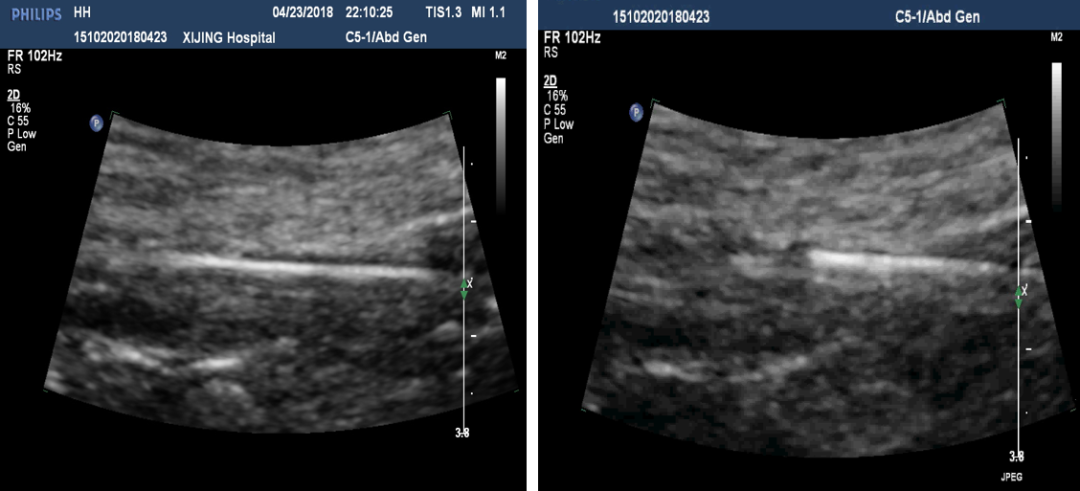

手术操作:系统溶栓治疗3天,症状未缓解,考虑其血栓时间较长,超声引导下行右髂动脉覆膜支架置入术

图:超声引导髂动脉覆膜支架置入术

图:髂动脉支架置入术后

图:二期开通右侧股浅动脉